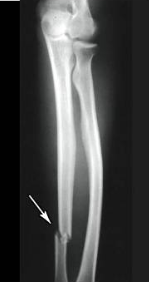

spiral fracture